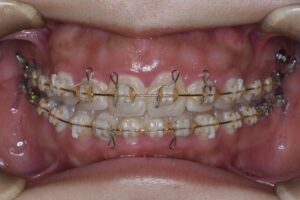

親知らずによって持ち上げられていた臼歯部を圧下していく。臼歯部を圧下しつつ、

前歯を咬合させるように顎間ゴムで力を少しずつかけていく。

少しずつ少しずつ